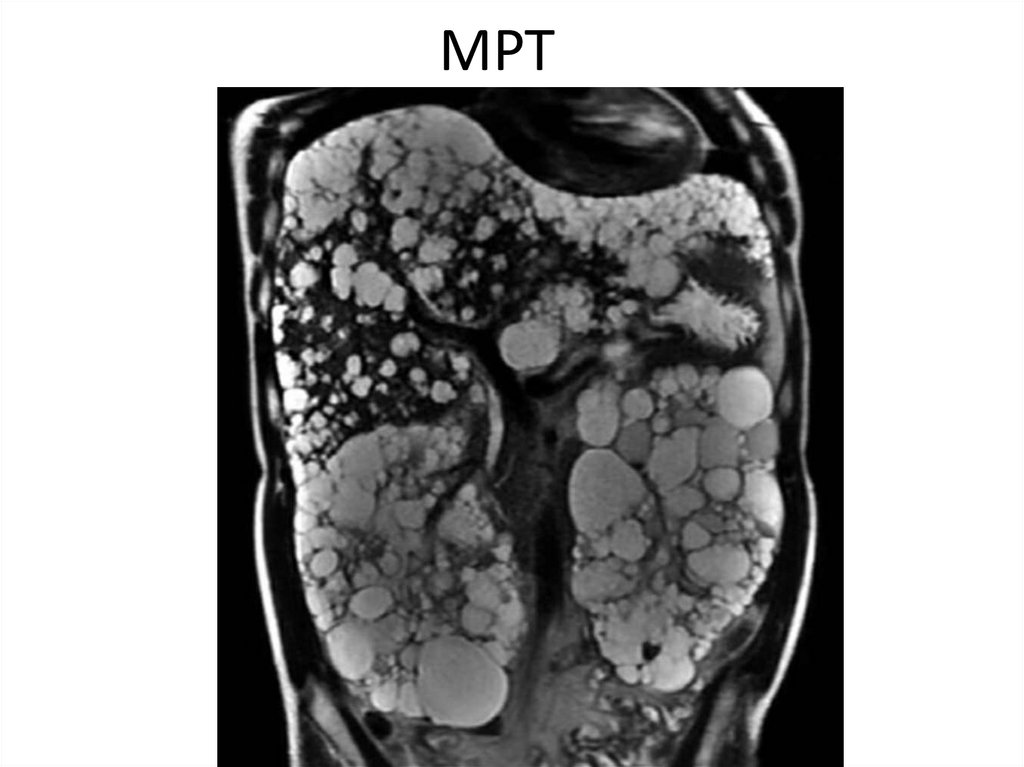

МРТ